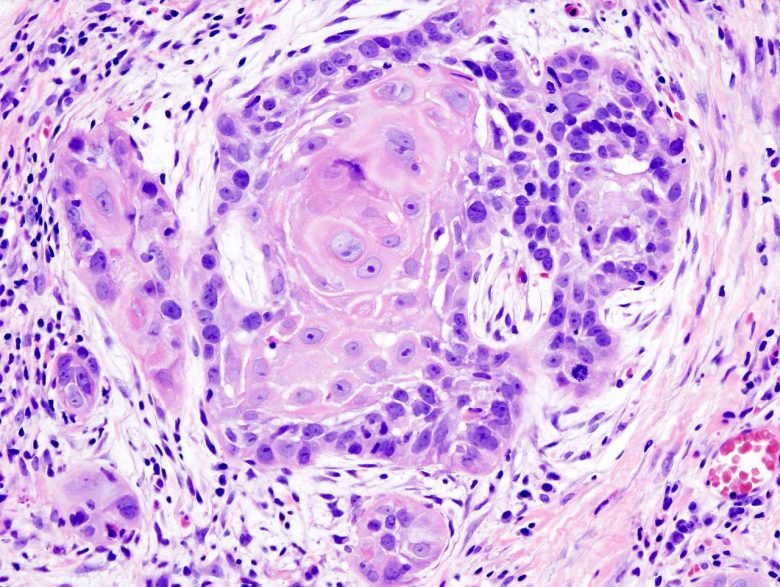

Thymoma and thymic carcinoma

“Thymomas and thymic carcinomas are rare tumors that form in cells on the thymus [a gland behind the breastbone that produces T-cells, a type of white blood cells].

“Thymomas grow slowly and rarely spread beyond the thymus. Thymic carcinoma grows faster, often spreads to other parts of the body, and is harder to treat.”

You can learn more here.

Image Credit: Humpath / Wikimedia Commons.